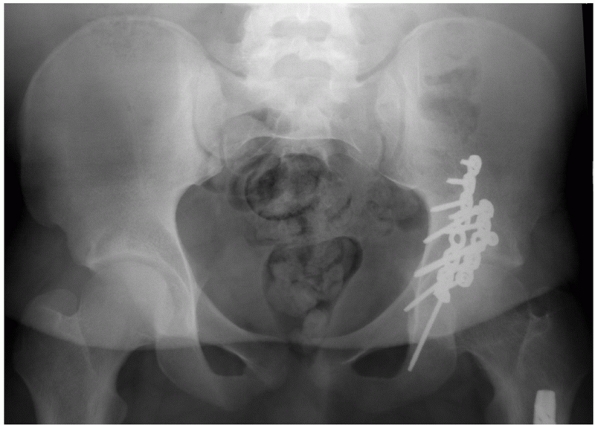

FIGURE 45-5 An 18-year-old 390-pound man (A) was involved in a motor vehicle accident. Anteroposterior radiograph (B) of the hip and selected two-dimensional computed tomography section (C) show a T-type fracture of the acetabulum and an ipsilateral fracture of the femoral shaft (D). Retrograde nailing was used to stabilize the femur (E) followed by acetabular fixation 2 days later (F) using the Kocher-Langenbeck approach. (Copyright Berton R. Moed, MD.)